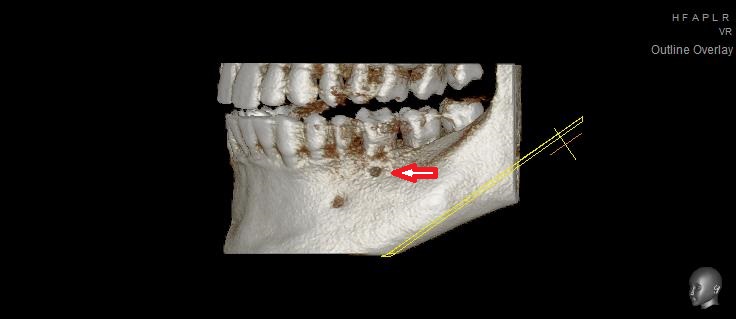

На этой проекции видно повреждение поверхности кости от кисты.

(отверстие, которое вы видите слева, чуть ниже — место выхода нижнечелюстного нерва)